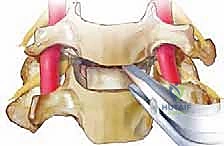

الخطوة 2: الشق الجراحي الأمامي (The Anterior Approach)

لماذا "أمامي"؟ الوصول إلى العمود الفقري من أمام الرقبة (عادة عبر شق أفقي صغير يتراوح بين 3 إلى 5 سم في أحد ثنيات الجلد الطبيعية) يسمح للجراح بالوصول إلى الأقراص الفقرية دون الحاجة إلى قطع عضلات الرقبة الخلفية القوية أو إزعاج الحبل الشوكي بشكل مباشر. يقوم الجراح بإزاحة القصبة الهوائية والمريء والأوعية الدموية بلطف للوصول إلى العمود الفقري.

الخطوة 4: استئصال القرص الغضروفي (Discectomy)

باستخدام أدوات ميكروسكوبية دقيقة، يتم تفريغ وإزالة القرص الغضروفي التالف بالكامل. يتم كشط الغضروف حتى الوصول إلى السطح العظمي للفقرتين العلوية والسفلية.

الخطوة 5: تخفيف الضغط العصبي (Decompression)

هذه هي المرحلة الأهم والأكثر حساسية. يقوم الجراح بإزالة أي نتوءات عظمية (Osteophytes) أو أجزاء من الغضروف الممزق التي تضغط على الأعصاب الشوكية أو الحبل الشوكي، مما يعيد للقناة الشوكية اتساعها الطبيعي.